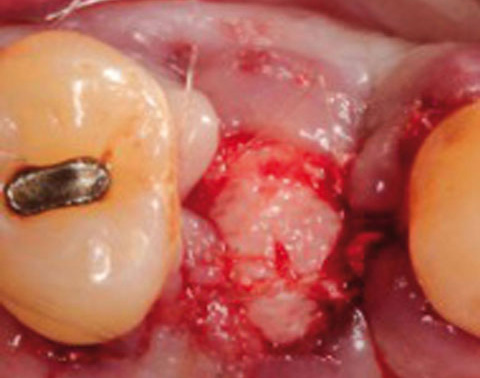

Ein lokaler dreidimensionaler Defekt würde normalerweise mit technikempfindlichen Knochenblöcken behandelt werden.

Durch die Verwendung einer OSSIX® Plus-Membran mit einer Titanschraube als stützender „Zeltstange“ (tent-pole) konnte Randelzhofer zeigen, dass sich derartige Defekte auch durch die Kombination mit partikulärem Knochenersatzmaterial regenerieren lassen.6

Behandlung eines ausgeprägten Knochendefekts in der ästhetischen Zone mit OSSIX® Plus-Membran auf einer Titanschraube als „Zeltstange“ und partikulärem Knochenersatzmaterial (li und Mi). Nach 5 Monaten war der Defekt optimal regeneriert, sowohl in vertikaler als auch in horizontaler Dimension (re).